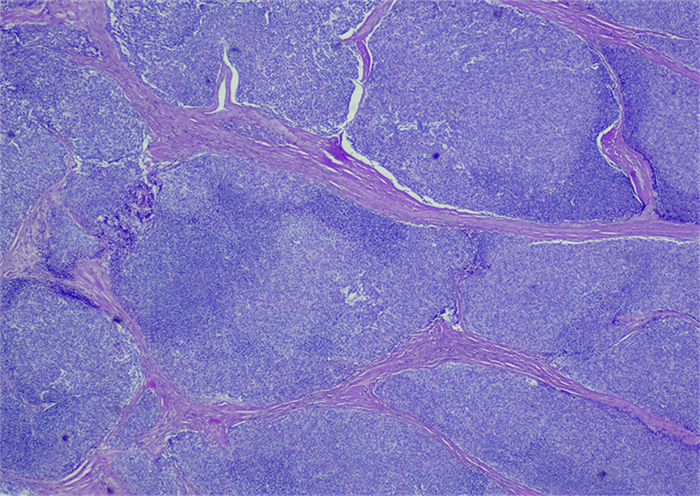

胸腺瘤的临床病理学研究:深入了解罕见肿瘤的病理特征

摘要:胸腺瘤是一种罕见的肿瘤,其病理学特征对于准确诊断和个体化治疗具有重要意义。本文综述了胸腺瘤的临床病理学研究进展,包括病理分类、组织学特征、免疫组化标记和分子病理学等方面的研究,以期为胸腺瘤的病理诊断和治疗提供新的视角和策略。引言胸腺瘤是一种发生在胸腺中的...